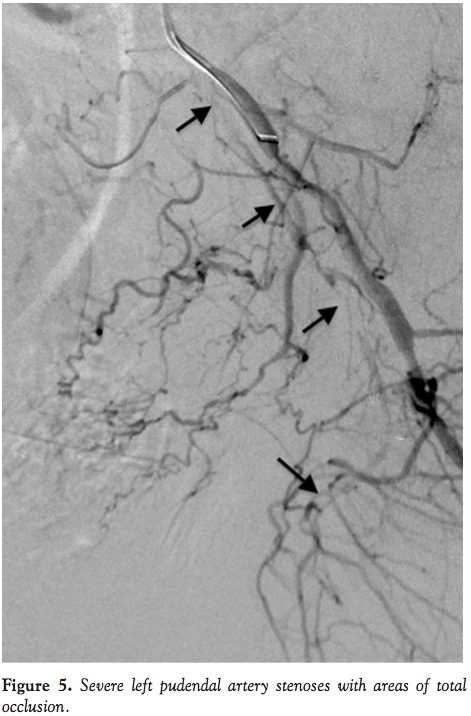

A 12 cm, 5 Fr sheath was placed in the right common femoral artery. Non-selective angiography was performed with a 5 Fr pigtail catheter in the descending abdominal aorta demonstrating bilateral occlusion of pudendal arteries. Angiography and successful endovascular revascularization of the left leg were then performed for identified severe PAD. This was performed via a 7 Fr, 45 cm sheath that was advanced with the tip in the left common femoral artery. The sheath was then pulled back to the ostium of the left internal iliac artery and a 0.035˝ wire was advanced into the left internal iliac artery. Due to the fact that the proximal segment of the left internal iliac artery was large and healthy, we advanced the sheath into the proximal segment over the 5 Fr IM catheter, which was used to redirect the wire and facilitate the sheath advancement. Selective angiography of the left internal iliac system was then performed at flat AP position, 30° RAO angulation, and 30° LAO angulation. It demonstrated diffuse, severe disease in the left internal pudendal artery with long segments of total occlusions (Figure 5). The left internal pudendal artery arose directly from the left internal iliac artery. A 5 Fr, angled, hydrophilic-coated catheter was advanced through the sheath and directed toward the left internal pudendal artery to facilitate wire passage through the lesions. However, a 0.014-300 cm coronary wire crossed only the proximal segment of the stenotic lesion and the rest of the lesion was crossed only after we used coronary 2.0 x 20 mm over-the-wire balloon for support. Multiple inflations up to 16 atm were then performed with the same 2.0 x 20 mm over-the-wire balloon. Since this patient had a very long total occlusion, suboptimal angioplasty result, and a history of diabetes, we decided to use drug-eluting stents to achieve an optimal angiographic result as well as to minimize the risk of restenosis. We used two 2.5 x 30 mm drug-eluting coronary stents that were deployed in overlapping fashion at 12 atm. This led to a good angiographic result (Figure 6). This patient was discharged the same day and had no complications. At clinical follow-up, the patient reported significant improvement in erectile function with good response to PDE5i therapy.